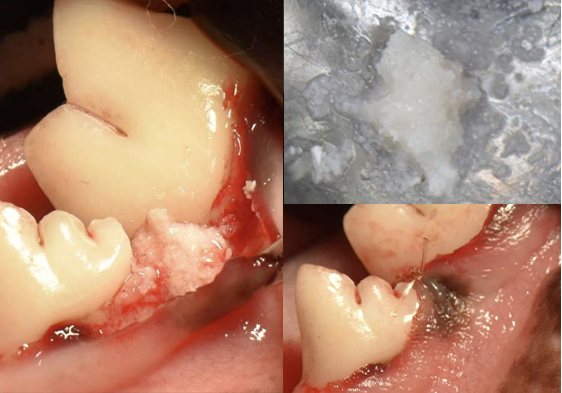

저희 치과센터는 단순한 스케일링을 넘어 구강 염증 치료, 외과적 발치, 치아 파절 치료 등 전문 진료를 제공합니다. 최신 장비와 숙련된 수의진이 맞춤형 치료와 예방, 사후 관리를 책임져 반려동물의 건강한 구강을 지켜드립니다.

• • 외과적 발치

• • 치아 파절 치료